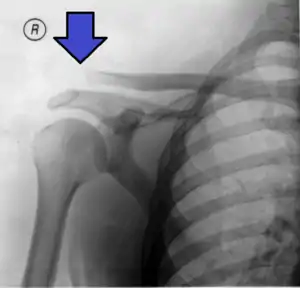

Type 3 AC joint separation on plain X ray

In a Type III AC separation both acromioclavicular and coracoclavicular ligaments are torn without significant disruption of the deltoid or trapezial fascia.[10] A significant bump, resulting in some shoulder deformity, is formed by the lateral end of the clavicle. This bump, caused by the clavicle's dislocation,[5] is permanent. The clavicle can be moved in and out of place on the shoulder. A radiographic examination will show the results as abnormal.